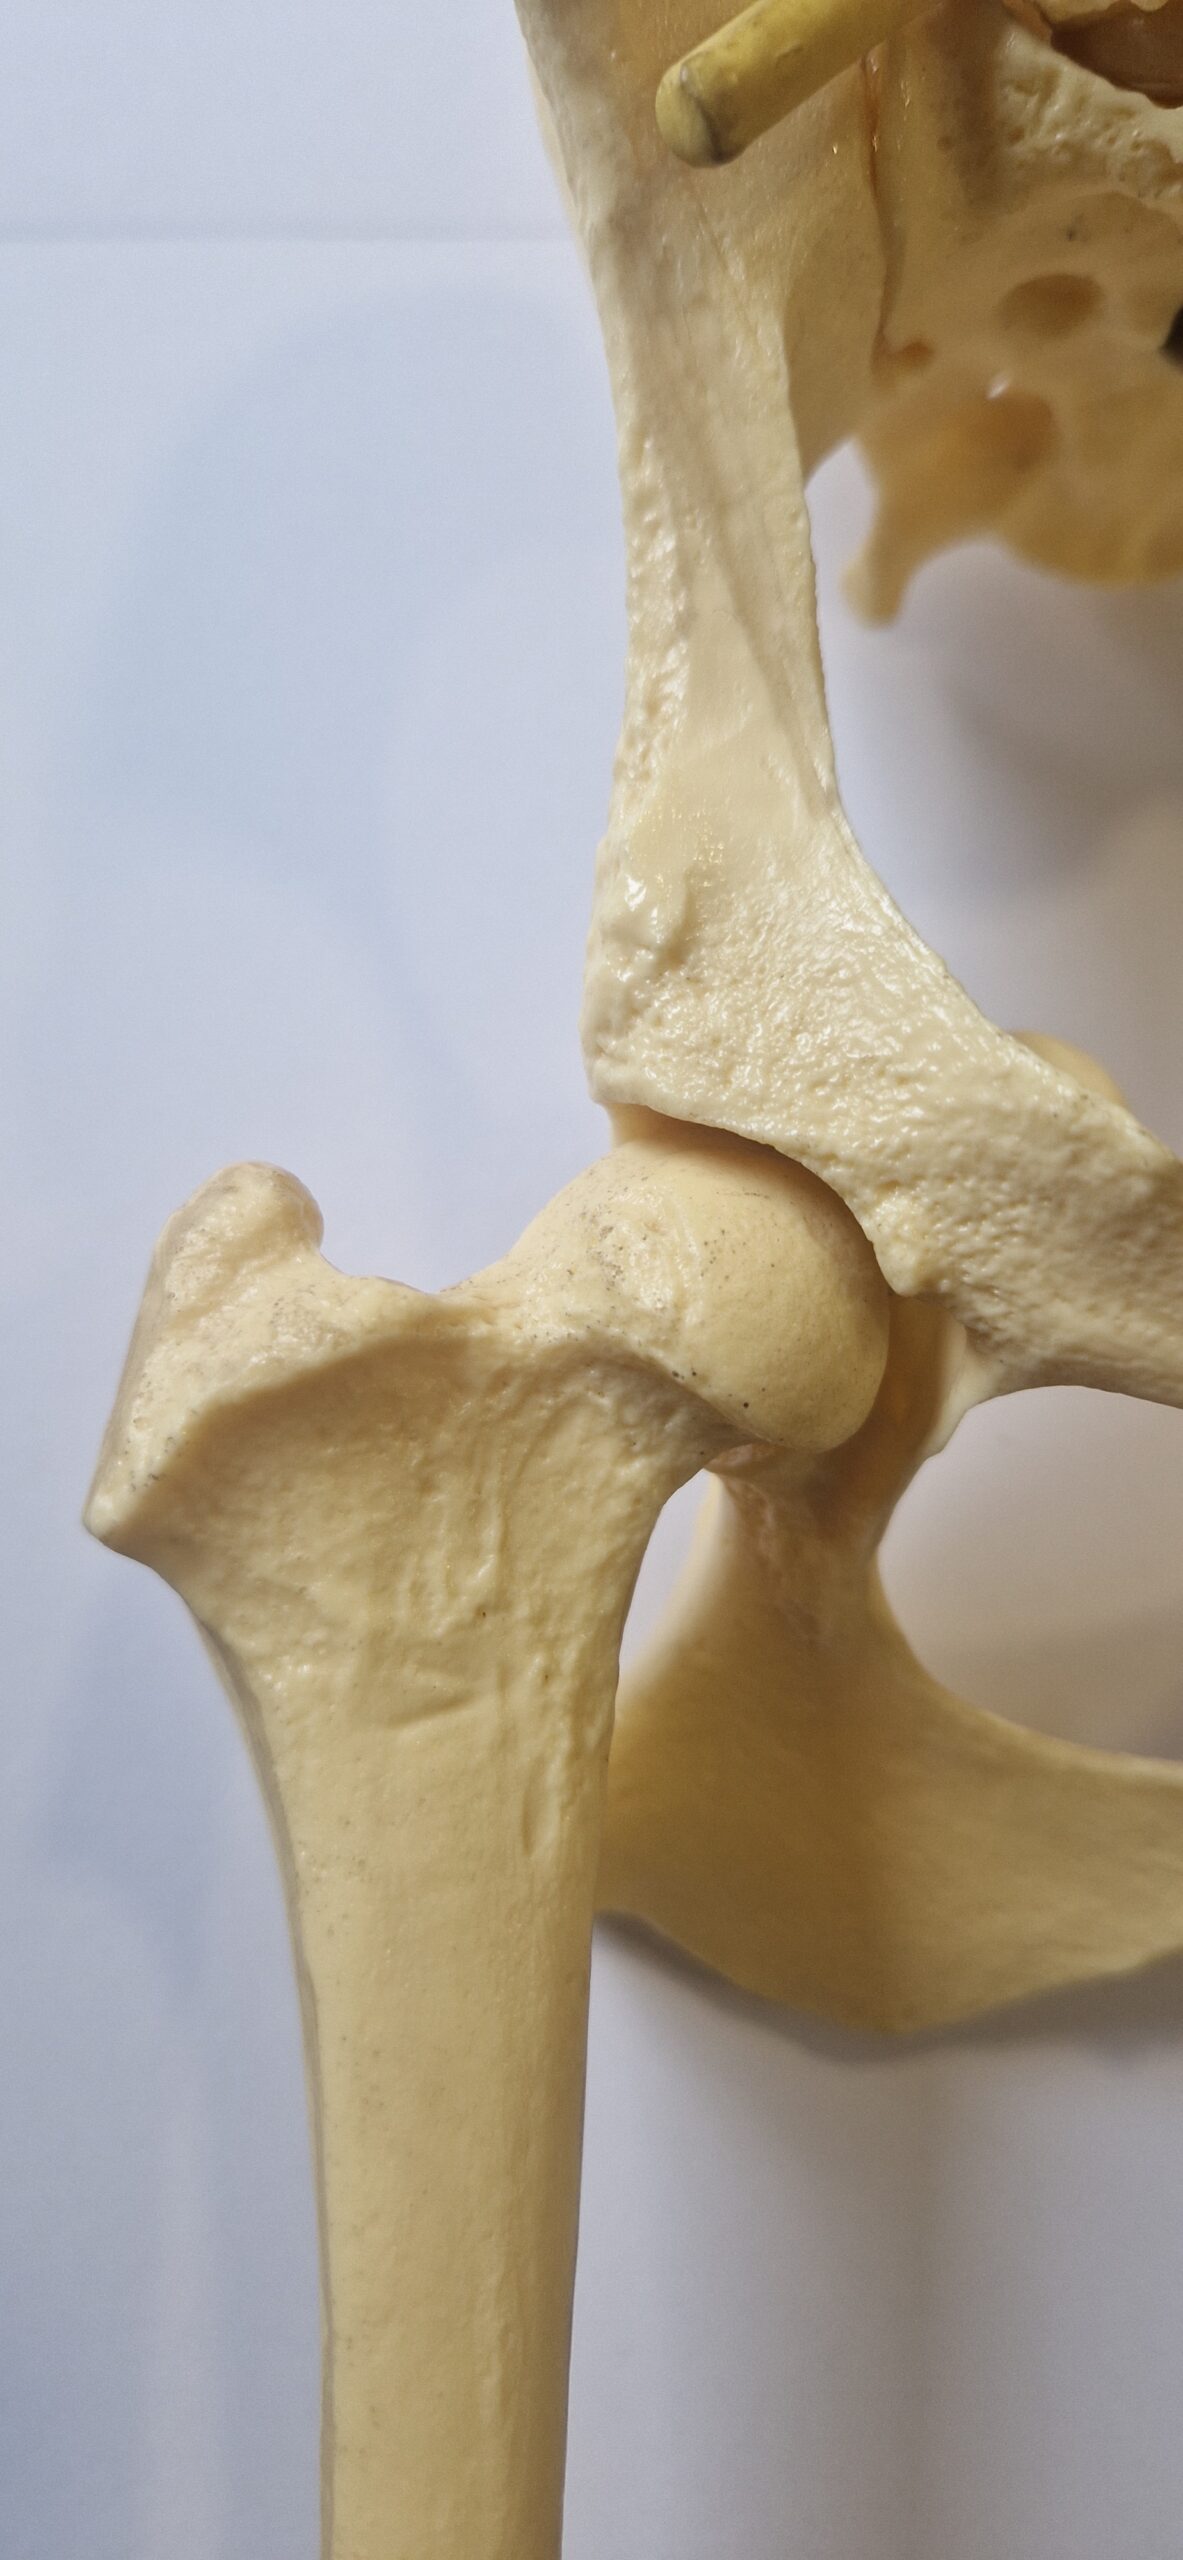

La dysplasie des hanches est une maladie articulaire. L’articulation de la hanche est formé par l’union de deux os, le bassin d’une part, et le fémur d’autre part. L’os du bassin possède deux cavités appelées « acétabulum ». Le fémur se termine en haut de la cuisse par une sphère appelée la « tête du fémur ». Dans les articulations en bonne santé, la tête de fémur va s’emboiter parfaitement dans l’acétabulum du bassin. Par contre chez certains chiens, cette emboitement n’est pas optimal! La tête du fémur est moins arrondie, la cavité du bassin moins bien creusée et recouvre moins bien la tête du fémur… il y a une instabilité plus ou moins marquée dans l’articulation.

hanche idéale

hanche légèrement instable

hanche fortement instable

Comme expliqué plus haut, l’articulation de la hanche est formée par l’union de deux os, l’acétabulum du bassin et la tête du fémur. La tête du fémur est maintenue bien enfoncée dans l’acétabulum par le ligament rond représenté par un large élastique blanc et bleu dans les images plus haut. Chez le chien dysplasique, dès l’âge de 1 mois (eh oui quand il est chiot!) ce ligament rond va prendre un aspect légèrement œdémateux et perdre quelques fibres. Cela va lui procurer une plus grande laxité et rendre l’articulation de la hanche moins stable. La tête du fémur va bouger légèrement dans la cavité acétabulaire. Il va y avoir à chaque mouvement, à chaque choc, des micros-traumatismes sur le cartilage de cette tête fémorale et de la cavité acétabulaire du bassin. Cela va conduire à un remodelage de ces 2 surfaces articulaires. La cavité sera moins creusée, la tête fémorale sera moins ronde. Ces phénomènes vont encore plus accentuer l’instabilité articulaire.